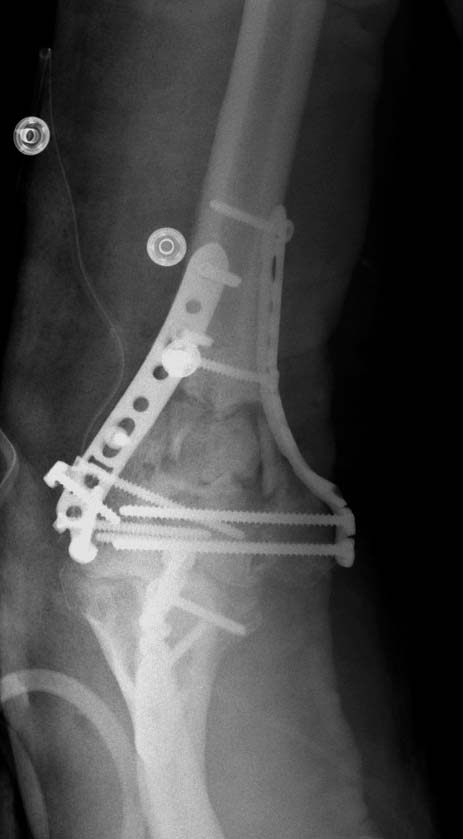

Примеры: первому более 15 лет фиксирован шурупом и tension band

technique, а второй перелом открытый больной 80 лет, после наружного

фиксатора в первом этапе и окончательная фиксация вторично. Третьий раз

внесуставная остеотомия...